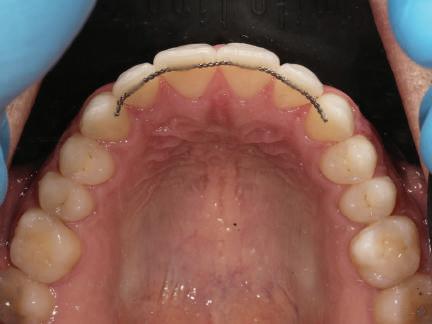

closed.

В горната челюст се затварят пространствата с дъга .016SS и верижка. 5-и месец На 5-ия месец след залепяне на брекетите в долната челюст е поставена стоманена дъга 16 x 22 SS с четвъртито сечение, омега луп и тай бек. В горната челюст е поставена дъга 17 x 25 NiTi. Поради липсата на стабилни оклузални контакти са поставени лингвални верижки в областта на моларите, за да се предотврати нежелана ротация на 7-ите зъби. 6-и месец На 6-ия месец от началото на лечението са екстрахирани долните първи премолари, поставена е дъга 16 x 22 SS със затваряща чупка teardrop. Чупката се активира всеки месец по 1 мм с чинч-бек. клиничен случай | ортодонтия СТЪПКИ НА ЛЕЧЕНИЕТО Начало на лечението Лечението започва с поставяне на апарат за бърза експанзия в горната челюст. През първия месец от лечението са направени 24 оборота на апарата за експанзия. Залепени са брекети в долната челюст, поставена е дъга 17x25 CuNiTi, като са предпи сани клас 3 ластици (1/4”,4 1/2 oz) по време на сън, за да се осигури контрол върху торка на долните резци. Фиг. 2а Фиг. 3a Фиг. 4a Фиг. 3b Фиг. 4b Фиг. 3c Фиг. 4c Фиг. 3d Фиг. 4d Фиг. 3e Фиг. 4e Фиг. 5a Фиг. 5b Фиг. 5c Фиг. 5d Фиг. 5e Фиг. 6a Фиг. 6b Фиг. 6c Фиг. 6d Фиг. 6e Фиг. 7a Фиг. 7b Фиг. 7c Фиг. 7d Фиг. 7e Фиг. 2b Фиг. 2c Фиг. 2d

Dental Tribune Bulgarian Edition / октомври 2022 г.22 клиничен случай | ортодонтия 14-и месец В горната и долната челюст са поставени последни стоманени дъга с омега луп и тай бек – 17 x 25 SS с четвъртито сечение. Назначени е ластик за средната линия в комбинация с клас 3 ластик (1/4”, 6 1/2 oz). Контролни рентгенографии 13-и месец Екстракционните пространства са затворени. Направена е контролна панорамна снимка за оценка позицията на корените. Взето е решение за презалепване на брекетите на 12, 22 и пръстените на 36 и 46. 21-ви месец Средната линия в горната и долната челюст съвпадат. Ластиците са спрени. Свалени са пръстените и брекетите в горната и долната челюст, зигзаг ластици не са използвани поради благоприятните оклузални взаимоотношения. Фиг. 11j Ортопантомография в края на лечението. Фиг. 11k Телерентгенография след края на лечението. Фиг. 11l Анализ на телерентгенографията след лечението. Фиг. 11m Последователност на дъгите в горната и долната челюст Фиг. 11n Суперимпозиция на PreOp и PostOp ортопантомографии. 10-и месец Затварянето на пространствата е предвидимо и контролирано, без да се отварят пространства в зъбната дъга. Фиг. 8a Фиг. 8b Фиг. 8c Фиг. 8d Фиг. 8e Фиг. 10a Фиг. 10b Фиг. 10c Фиг. 10d Фиг. 10e Фиг. 9a Фиг. 9b Фиг. 9c Фиг. 9d Фиг. 9e Фиг. 9f Фиг. 11a Фиг. 11f Фиг. 11j Фиг. 11l Фиг. 11m Фиг. 11n Фиг. 11k Фиг. 11g Фиг. 11h Фиг. 11i Фиг. 11b Фиг. 11c Фиг. 11d Фиг. 11e